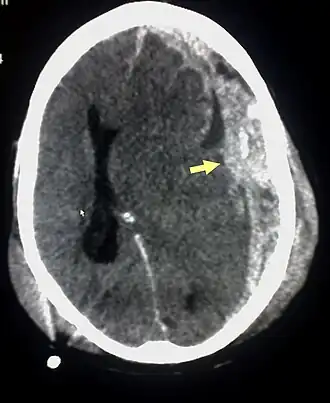

Os hematomas subdurais ocorrem mais freqüentemente no topo e partes laterais frontais e lobos parietais.[2][11] Também são frequentes na fossa posterior do crânio, e perto da foice cerebral e do tentório.[2] Ao contrário hematomas epidurais , que não podem expandir-se através das suturas do crânio, os hematomas subdurais podem expandir-se no interior do crânio, criando uma forma côncava que se segue a curva do cérebro, bloqueados apenas pelas reflexões durais como o tentório e a foice cerebral. Em uma tomografia computadorizada, os hematomas subdurais são classicamente em forma de crescente, com uma superfície côncava distal ao crânio. No entanto, eles podem ter uma aparência convexa, especialmente na fase inicial do sangramento. Isso pode causar dificuldade em distinguir entre as hemorragias subdural e epidural. Um indicador mais fiável de hemorragia subdural é o envolvimento de uma parcela maior do hemisfério cerebral, já que pode cruzar as linhas de sutura, ao contrário de uma hemorragia epidural. Sangue subdural também pode ser visto como uma densidade de camadas ao longo da membrana tentorial . Isto pode ser um processo crónico estável, uma vez que o sistema de alimentação é de baixa pressão. Em tais casos, os sinais sutis de hemorragia como o apagamento dos sulcos ou o deslocamento mediano da junção entre a matéria cinzenta e matéria branca podem ser aparentes. Um sangramento crônico pode ter a mesma densidade do tecido cerebral (chamado isodenso ao cérebro), o que significa que ele vai aparecer na TC como o mesmo tom que o tecido cerebral, potencialmente mascarando a lesão.